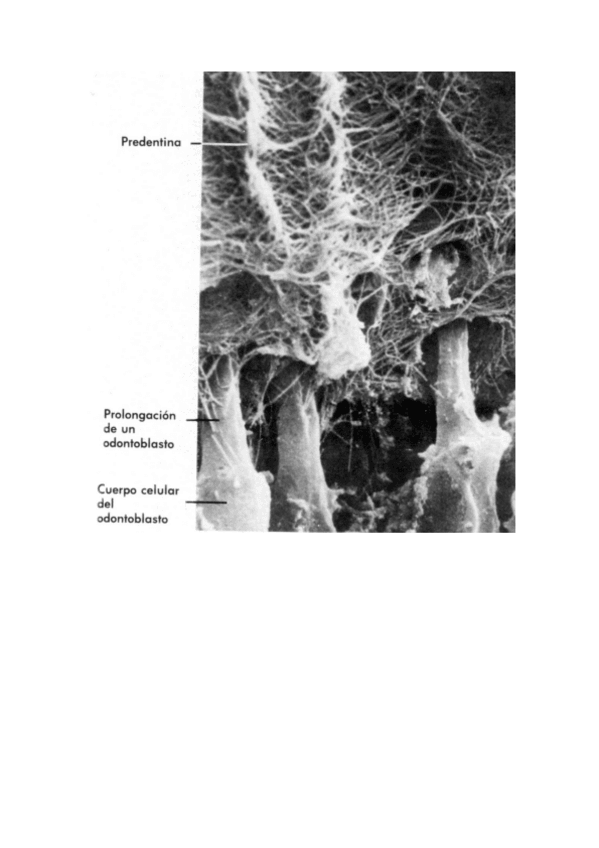

He publicado nuevos apuntes de 1º Ampliación de la Histología Bucodental: TEMA_16_LA_DENTINA.PDF